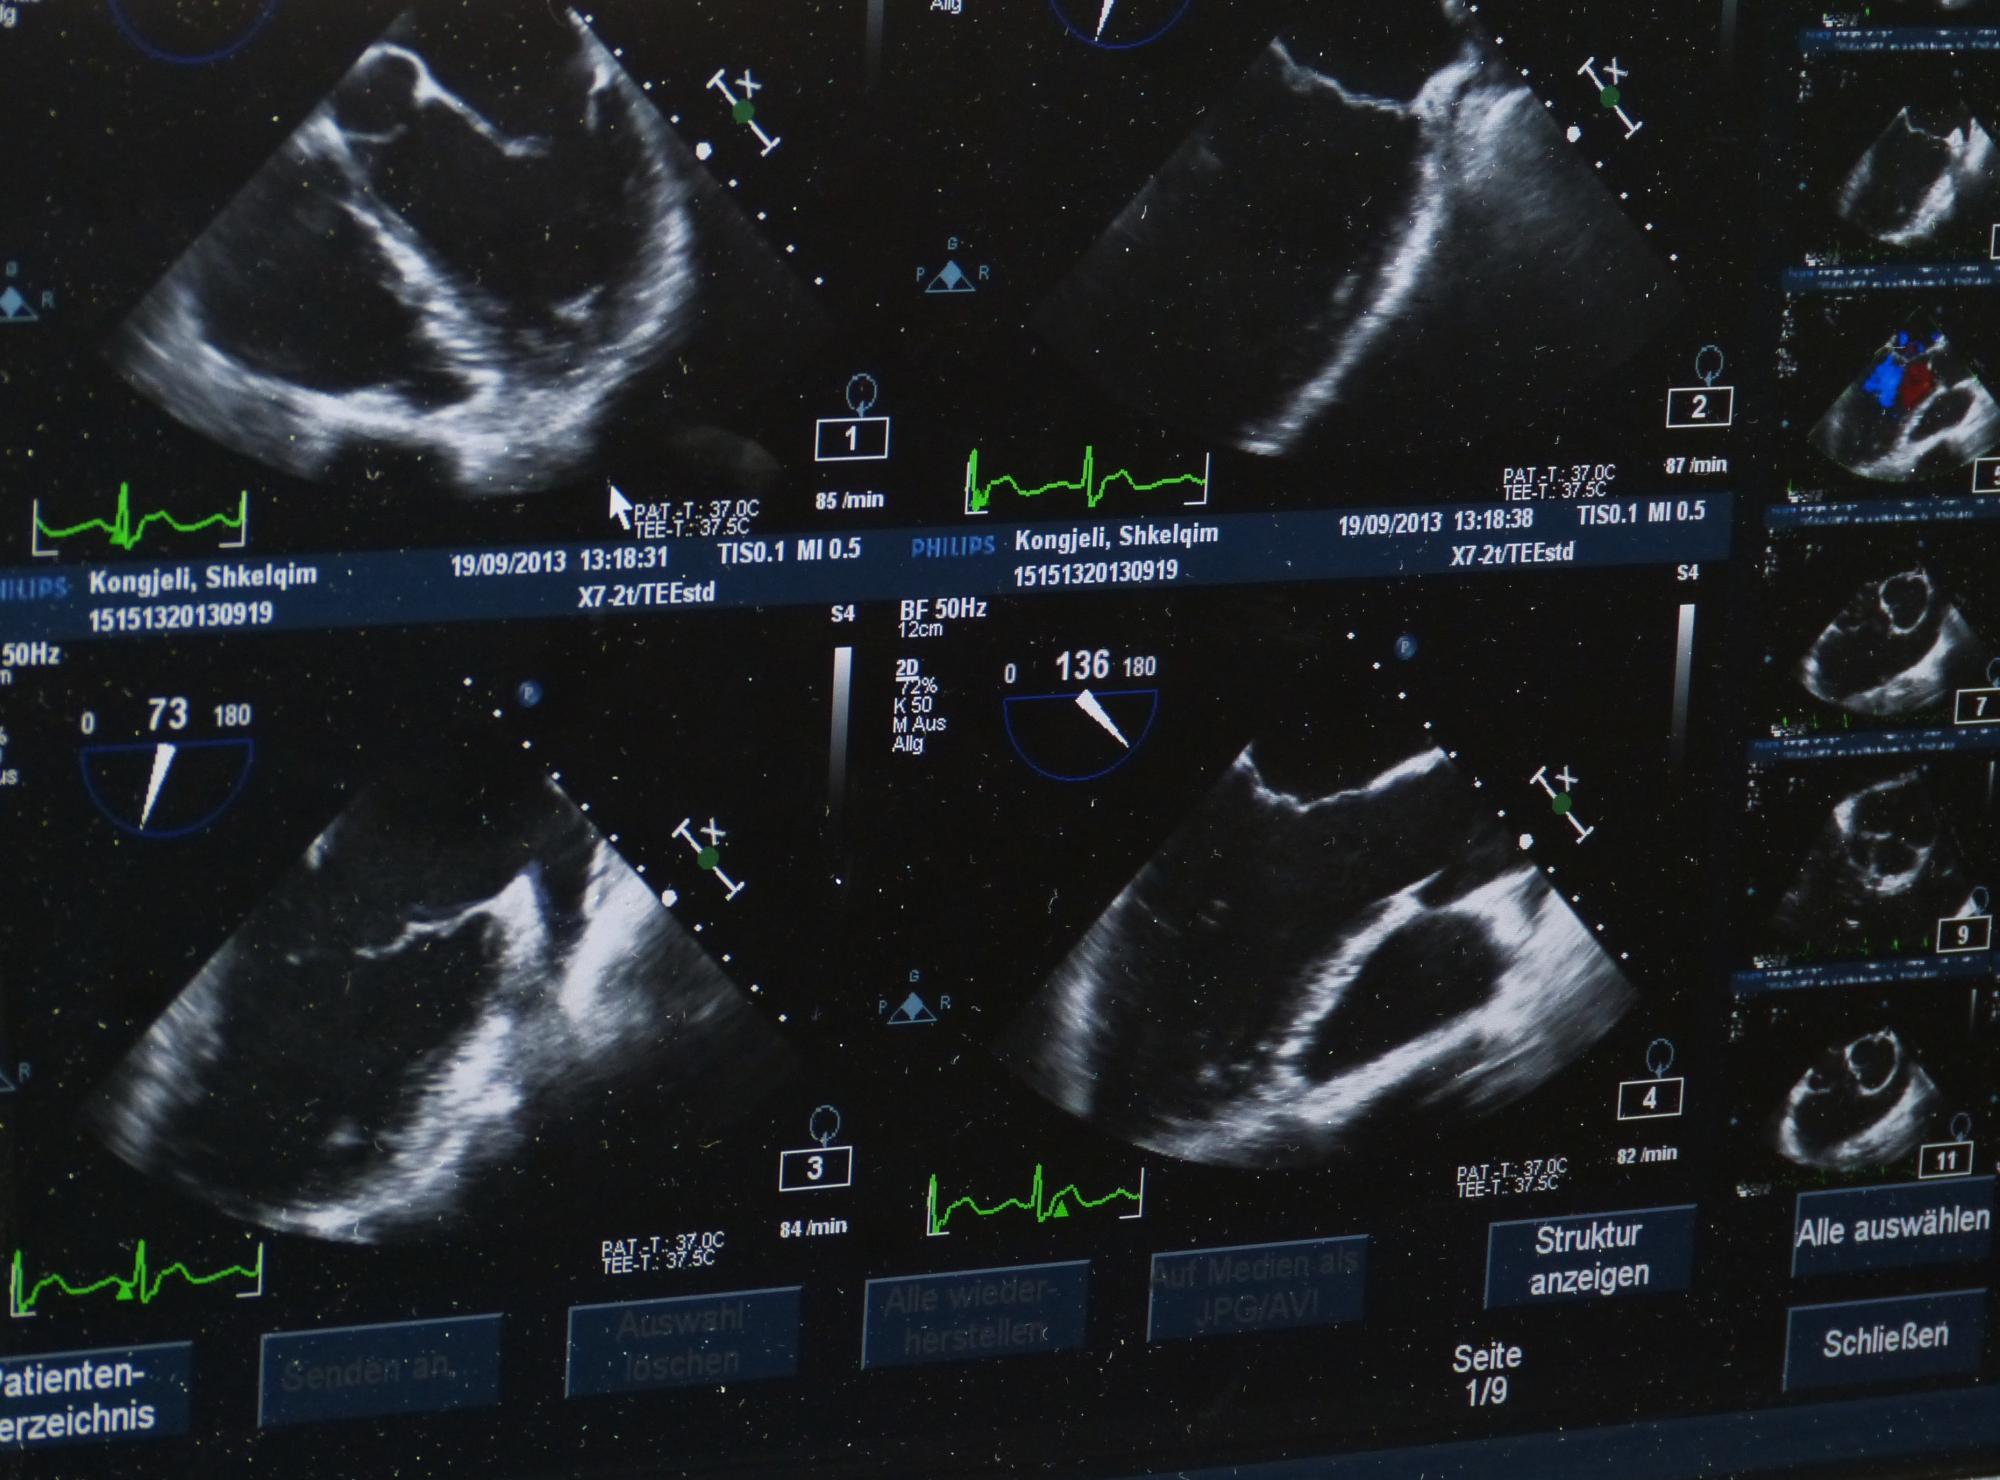

Nyt projektsamarbejde vil flytte grænsen for, hvad lægerne kan se på ultralydsskanninger. Ved at indsprøjte små luftbobler i blodet og følge bevægelserne, vil man kunne se blodets strømning ud i de mindste kar. Det bliver muligt at visualisere et blodkar på størrelse på 10 milliontedel meter, svarende til en tiendedel af et hår. Ved at vise og følge blodgennemstrømningen i vævet, kan det blive muligt at følge den direkte effekt af kemoterapi og strålebehandling af kræfttumorer meget tidligere.

Hidtil er forsøgene udført på rotter, og her var det muligt at se, hvordan blodet løber i de yderste dele af rottens nyre og dens hjerne. Ambitionen er, at teknikken skal kunne anvendes på mennesker, og her skal man kunne kompensere for bevægelserne fra vejrtrækning og hjertelag, mens skanningen skal kunne udføres i tre dimensioner dybere ned i kroppen end på rotter.

Projektpartnerne har i en årrække udviklet avanceret algoritmer og udstyr til medicinsk ultralyd. Dette har blandt andet resulteret i de første 3D metoder i verden, som kan måle blodets strømning i alle retninger. Disse vil blive videreudviklet og raffineret til superopløsnings-ultralydsbilleder, og projektet inkluderer udvikling af nye ultralydsprober, algoritmer, skannere og de indledende forsøg for metoden.